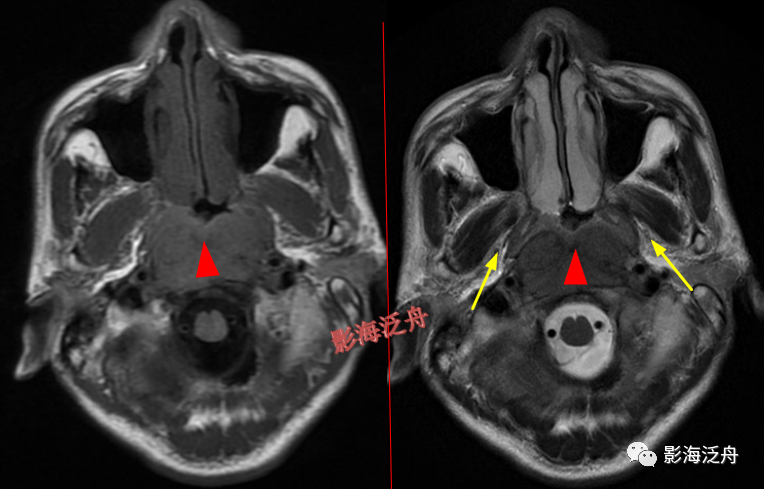

左侧岩尖部囊性病变(红箭头),患者未术,病理不明。MR对骨质结构显示不佳,因此很多读者会忽略掉颅内骨质病变的观察,很多颅内病变,如三叉神经鞘瘤、鼻咽癌等都会造成颞骨岩部(红色标注区)骨质破坏,因此,平时应对此处多加留意。黄箭头指听神经及内耳结构。

蝶骨骨纤维异常增殖症(红箭头),病灶内部可见特征性的囊变区(黄箭)。蝶骨的病变在MR上识别起来更为困难,因为蝶骨位于颅底部,此处骨骼、肌肉、脂肪等多种组织成分混杂,导致正常情况下也看起来非常乱。不要着急,慢慢学。